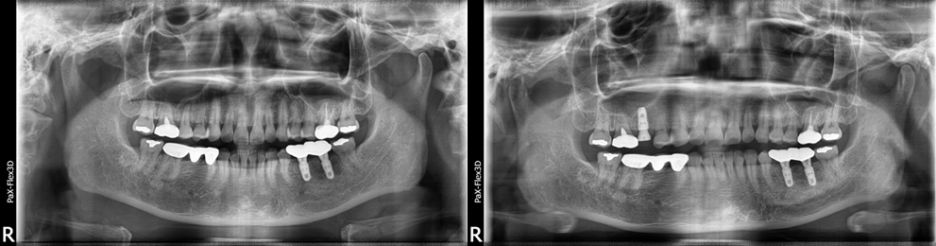

46세 여성

오른쪽 위 어금니 발치 후 뼈이식 진행하고 3개월 후 임플란트 식립

(전) 2021-07-16 (후) 2021-11-17